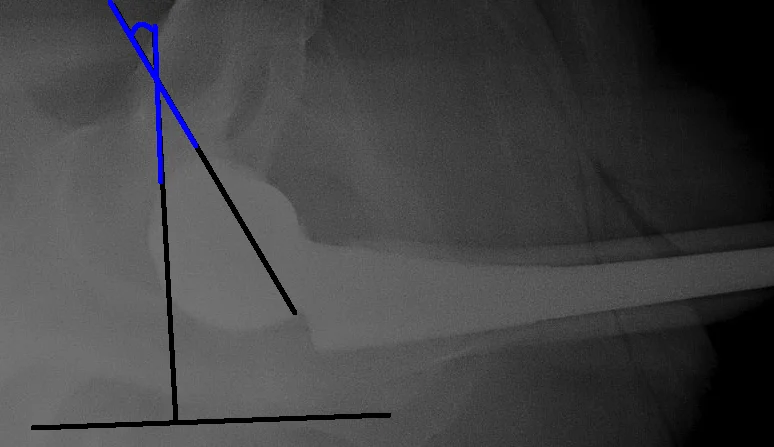

START BY EVALUATING CUP PLACEMENT

THEN EVALUATE STEM PLACEMENT.